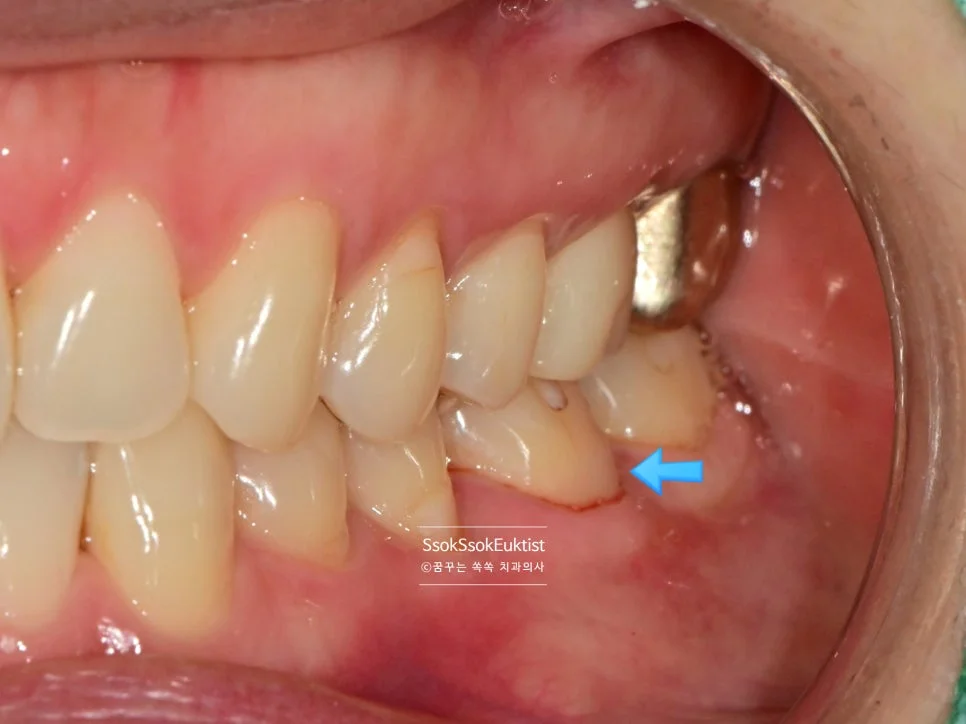

레진 치료 전 — V자 형태의 치경부 마모증

치아의 목 부분이 패여져 있는 모습입니다. 형태를 보면 U자라기보다는 V자에 가깝고, 즉 강한 교합력에 의해 치아 목 부분이 패였네요.